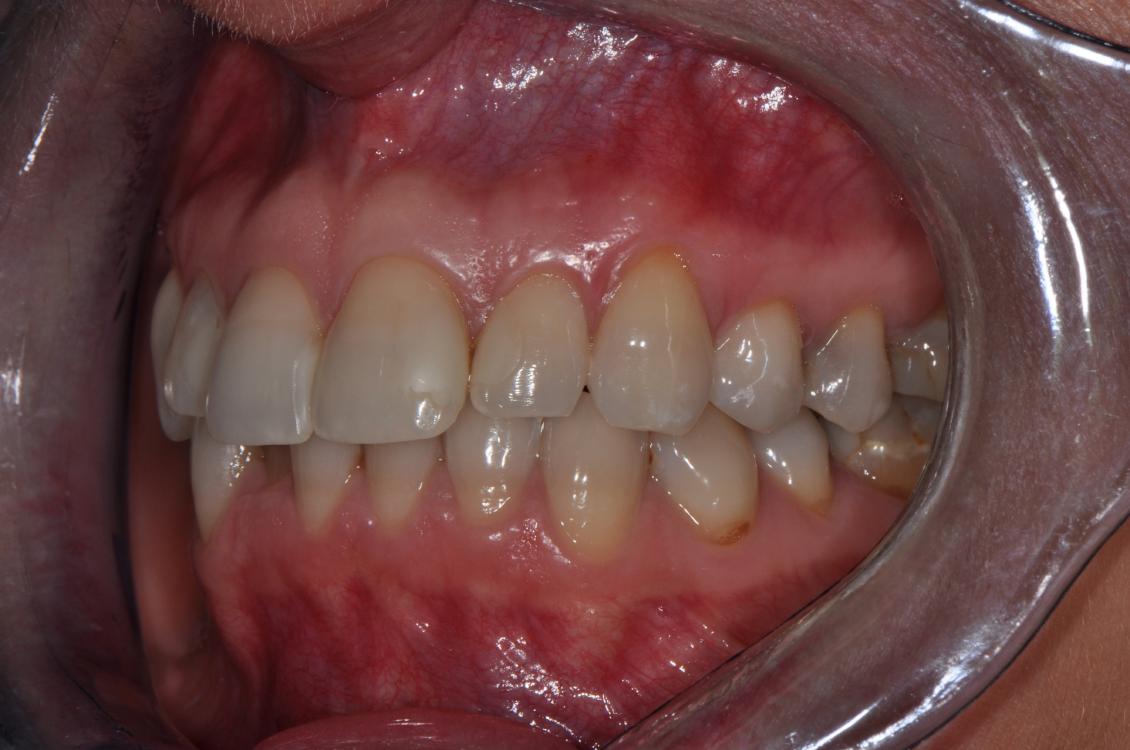

Wykonano zdjęcia uzębienia pacjentki (ryc. 2‑4). Przeprowadzono dokładne badanie mięśni żucia, zbadano ruchy żuchwy w trzech płaszczyznach – ruch otwierania jamy ustnej, ruch doprzedni oraz ruchy doboczne. Podczas otwierania zaobserwowano zbaczanie żuchwy w połowie ruchu, a następnie powrót do linii prostej. Bolesność mięśni żucia, stłoczenie zębów oraz nieprawidłowy tor ruchu żuchwy podczas otwierania nasuwał podejrzenie występowania problemów okluzyjnych.

Ryc. 2. Zdjęcie w pozycji maksymalnego zaguzkowania – strona lewa. Proszę porównać z ustawieniem zębów w artykulatorze (ryc. 8). Zmieniła się znacznie szpara przednio‑tylna i wychylenie zębów siecznych górnych.